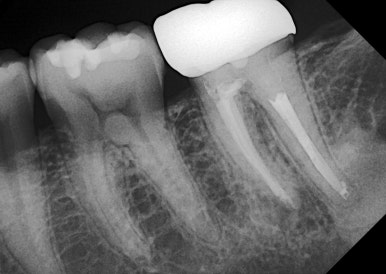

🦷 사용 임플란트: 메가젠 블루다이아몬드

이번 케이스에서는

👉 메가젠 블루다이아몬드 임플란트를 사용했습니다.

✔ 높은 강도

✔ 빠른 골유착

✔ 어금니처럼 힘 많이 받는 부위에 적합

👉 특히 저작력이 강한 부위에서

안정성이 뛰어난 제품입니다.